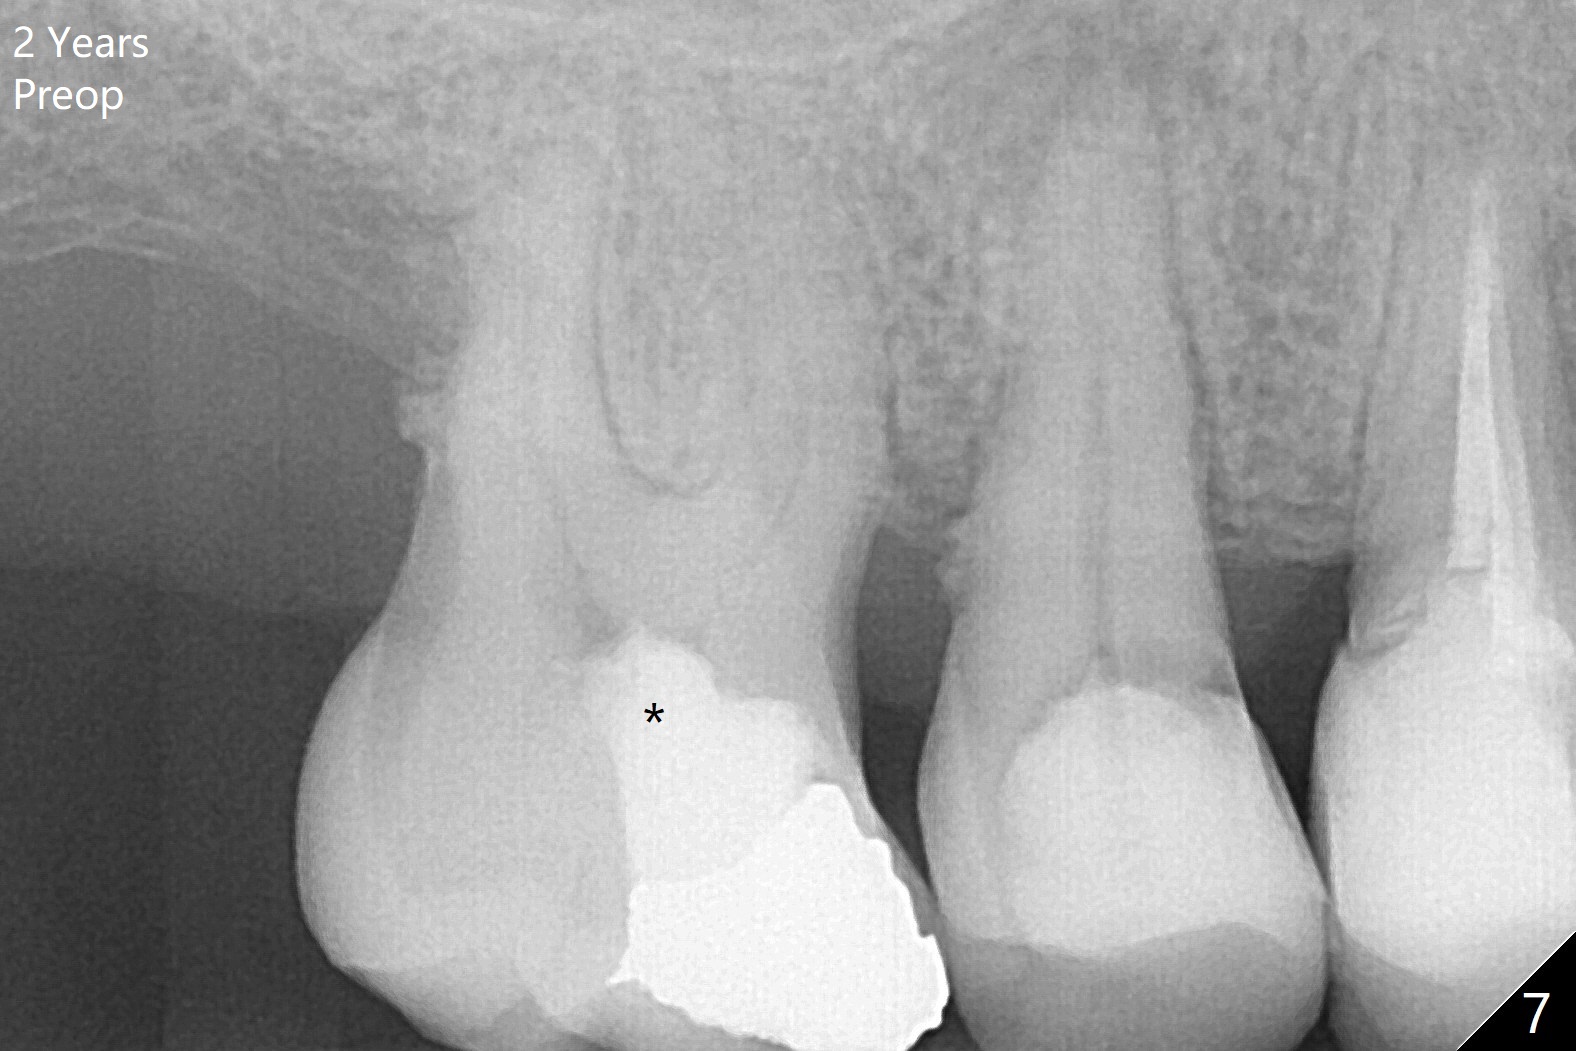

The female patient has limited mouth opening, complicated further by supraerupted opposing tooth. It is difficult to insert point drill and tap drill for #30 implant placement with guide. The former has to be inserted into the sleeve of the guide extraorally; two of them are placed intraorally together, while the tap drill is not used at all. When a 4.5x10 mm implant is placed, it is difficult to use #2 sensor to take PA. Finally a BW is taken with #2 sensor (Fig.1), while a PA is taken with #1 sensor (Fig.2). CT is taken to show clearance of the implant from the Inferior Alveolar Canal (Fig.3,4). To seat healing and later cemented abutments completely, a 5.5 mm profile drill is applied after implant placement; the outline is illustrated by red dashed line in Fig.1''. The elongated mesiolignual cusp of the tooth #3 has to be trimmed after placement of a 6x5 mm healing abutment. In fact trimming prior to osteotomy could solve the mouth opening partially. After removal of the 6x5 mm healing abutment, a 4.5x4(3) mm cemented abutment is incompletely seated (Fig.5 <) apparently due to proximity to the mesial crest (*). With reuse of a 4.6 mm profile drill, the abutment is fully seated (Fig.6), confirmed clinically by more clearance from the opposing tooth (Fig.7). Complete occlusal clearance is obtained by reduction of the opposing cusps without sensitivity since the tooth is nonvital (*). Return to No Deviation Xin Wei, DDS, PhD, MS 1st edition 05/28/2020, last revision 09/04/2020